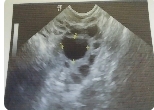

之所以有的患者需要降調(diào)有需要進(jìn)行促排,是因為促排卵是使用藥物促使多個卵泡同時生長,這樣會擾亂下丘腦-垂體-卵巢軸的調(diào)控機制。這種情況可能會導(dǎo)致排卵提前或還沒排出卵子,卵泡就已經(jīng)變成了黃體。很多時候為了避免這種情況發(fā)生,是需要在前期使用降調(diào)節(jié)治療,采用藥物干預(yù)下丘腦-垂體-卵巢軸的調(diào)節(jié)作用。前期降調(diào)節(jié)可以幫助卵泡生長更加容易被醫(yī)生控制,爭取獲得多個同步發(fā)育的成熟卵泡,并且盡量保證卵細(xì)胞質(zhì)量。